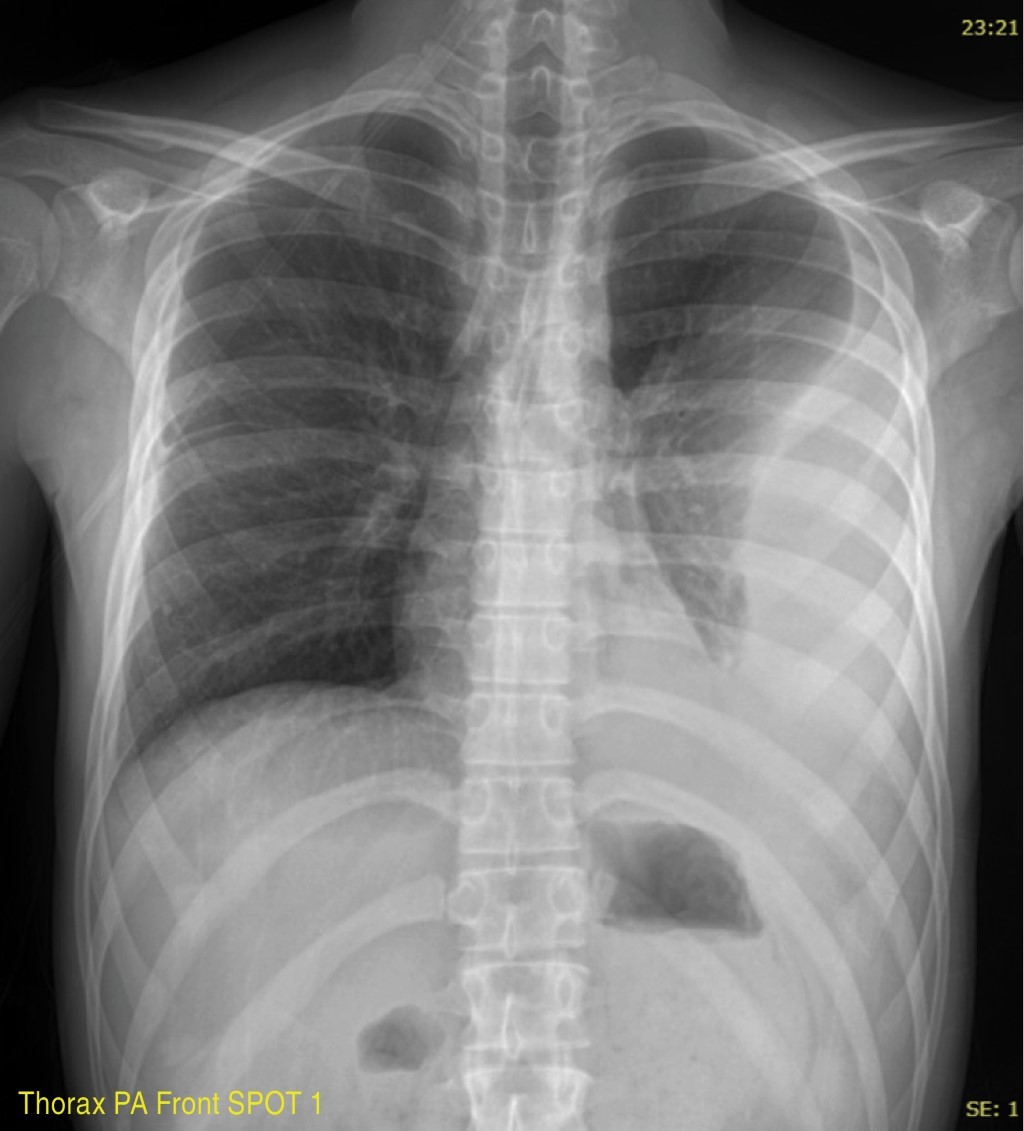

There are other radiological projections, such as expiratory radiography, which detects small pneumothoraxes and localized air trapping associated with foreign bodies, and the lateral decubitus projection with a horizontal beam that evaluates free fluid in the pleural cavity, among others.